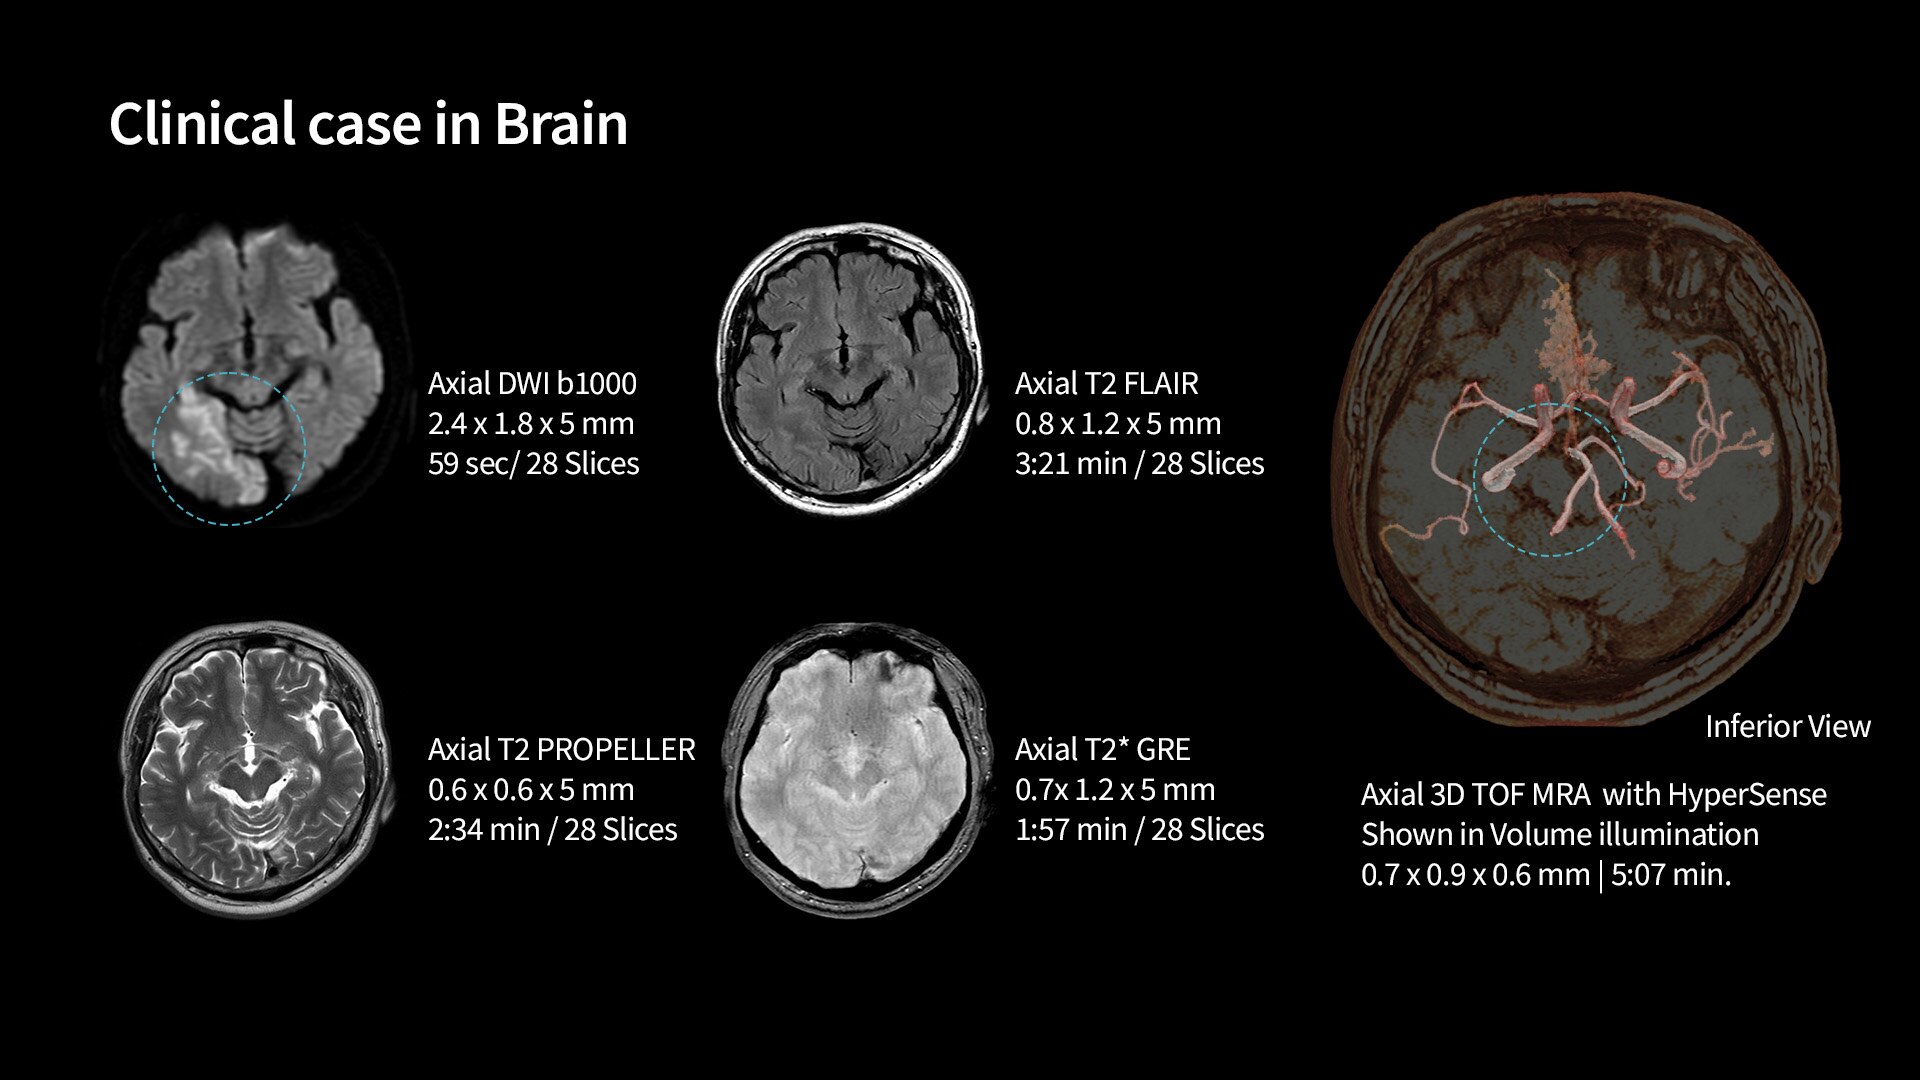

With SIGNA™ Prime, you don’t have to choose between accessibility and quality. We equipped SIGNA™ Prime with state-of the-art Total Digital Imaging (TDI) 2.0 technology. We paired that with the latest AI technology to generate images that are as easy to read as the system itself is to use. SIGNA™ Prime includes AIR™ Recon DL capability, the industry’s leading deep learning-based image reconstruction algorithm that works across all anatomies. AIR™ Recon DL improves image quality at the foundational level by leveraging raw data to remove image noise and ringing. It also improves SNR and image sharpness, enabling much shorter scan times.